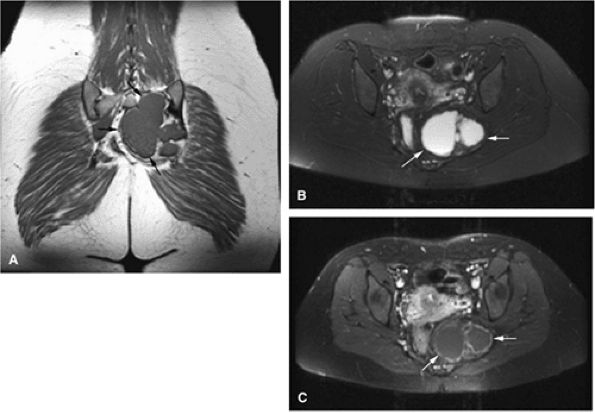

FIGURE 14-85 ● Plasmacytoma of the right ilium. (A) Coronal T1-weighted MR image reveals an intermediate-signal-intensity mass (arrows) with aggressive cortical transgression and soft-tissue extension. (B) Axial fat-suppressed T2-weighted fast spin-echo image shows hyperintense tumor and soft-tissue mass (arrows). (C) Axial fat-suppressed T1-weighted image following intravenous administration of contrast demonstrates non-enhancing central areas of necrosis (arrows).